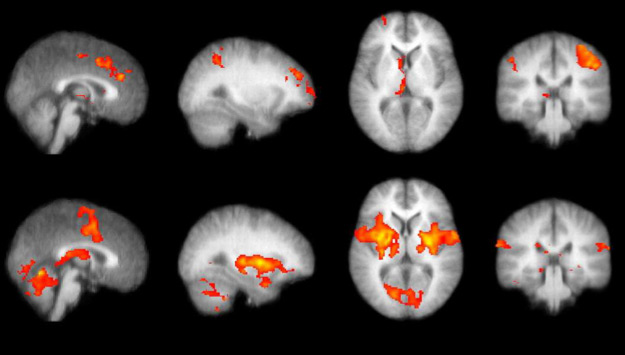

Da qualche decennio, le connessioni tra le aree della corteccia possono essere verificate anche in diretta con le immagini della risonanza magnetica funzionale, una tecnica che si basa sul fatto che nel momento dell’attivazione c’è un maggiore flusso di sangue nella regione corticale attivata.

Nell’immagine, le aree responsabili dell’ascolto e della produzione del linguaggio visualizzate in risonanza magnetica funzionale (fMRI).

Ora, le differenze anatomiche più importanti tra maschi e femmine sono state rilevate non a livello della materia grigia, ma a livello delle connessioni tra le aree della corteccia che avvengono attraverso i fasci nervosi che costituiscono la materia bianca, il connettoma a cui abbiamo appena accennato.

maschio-e-femmina-commettività

Sopra, cervello maschile; sotto, cervello femminile. In blu le connessioni che si sono sviluppate tra aree dello stesso emisfero; in arancione, tra aree di emisfero diverso. Immagine tratta da Sex differences in the structural connectome of the human brain Ragini Verma et al, University of Pennsylvania, PNAS, n ovembre 2013.

Lo studio da cui sono tratte queste immagini ha dimostrato che i maschi sono più connessi all’interno di ciascun emisfero, le femmine tra i due emisferi.

Il che grosso modo significa che i maschi si specializzano verso l’integrazione tra movimento e percezione, mentre le femmine tra logica e intuizione.

Così, anche se ad ogni punto della corteccia corrispondano specifiche funzioni o aree del corpo, l’attivazione di una parte produce normalmente anche l’attivazione di altre regioni. Non solo nel caso degli stimoli e degli sforzi di memoria visualizzati in queste immagini fMRI.

fmriPAIN

Attivazione di aree cerebrali per uno stimolo doloroso e per lo sforzo per riconoscerne o ricordarne la fonte. Sopra, le aree cerebrali che si attivano durante il compito di descrivere dove i soggetti ricevevano lo stimolo doloroso; sotto, e l’effetto dello stimolo. Immagine tratta da Brain Mechanisms Supporting Spatial Discrimination of Pain pubblicato su The Journal of Neuroscience (marzo 2007) da Yoshitetsu Oshiro et al.